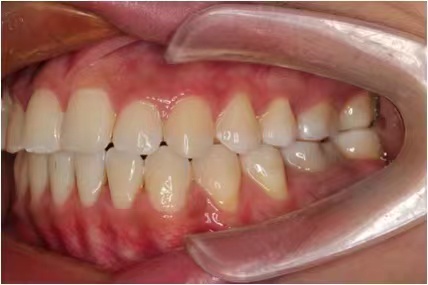

情况:不接受外科手术,在当地做了1年半的矫治,遇到困难无法进行。由外地正畸同行推荐来上海寻求非手术矫治的二手病例。武广增老师接收时的错合畸形情况,呈现严重的骨性反合偏合及侧方开合(图1-图10)。由于推荐其去口腔医院接受正颌外科手术遭到拒绝,武广增老师通过专业的检查、分析,制定一套详细的治疗计划,采用了磨牙推进器技术、武式辅弓技术等特色正畸手段获得明显效果(图2-1~图2-9)。治疗结束后也拍摄了相关照片(图3-1~图3-9)。

矫治后

图3-2